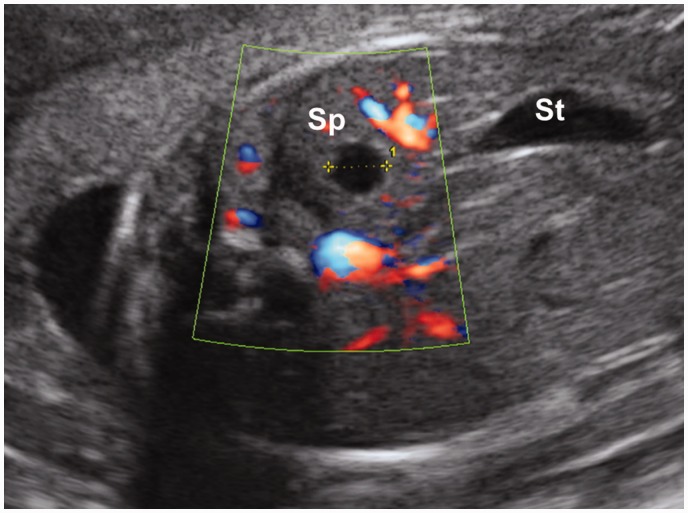

A closed sac located in the spleen.